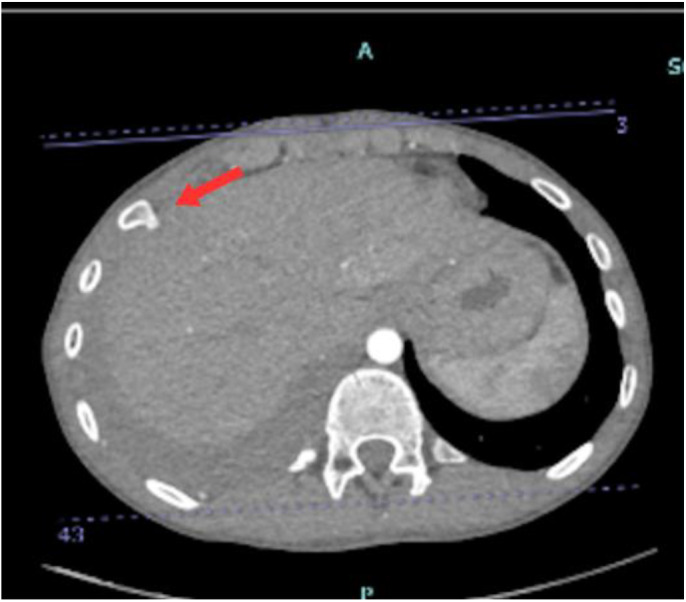

Exostosis, or osteochondroma, is an irregular bone growth commonly occurring near the femur, scapula, humerus and ribs. It can be a single isolated lesion or multiple lesions as in hereditary multiple exostoses (HME) which is a genetic autosomal dominant disorder. Although often asymptomatic, complications such as haemothorax are rare and have serious implications if not promptly recognised. We report a 15-year-old male patient who presented to a tertiary care hospital in Muscat, Oman, in 2023 who presented with progressive chest pain and dyspnoea. The patient had a family history of HME. Video-assisted thoracoscopic surgery (VATS) confirmed the osteochondromatous lesions on the 8th rib, which was causing the haemothorax. The lesion was resected and post-surgery, the symptoms resolved. No recurrence was documented up to the time of writing this report.